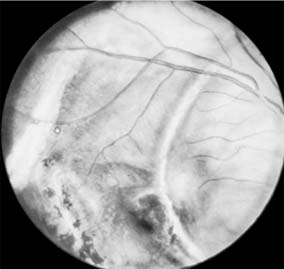

Figure 19-3

Figure 19-3: Hole in retina, macular area, posttraumatic.

Figure 19-4

Figure 19-4: Choroidal ruptures. (Photo by Diane Beeston.)